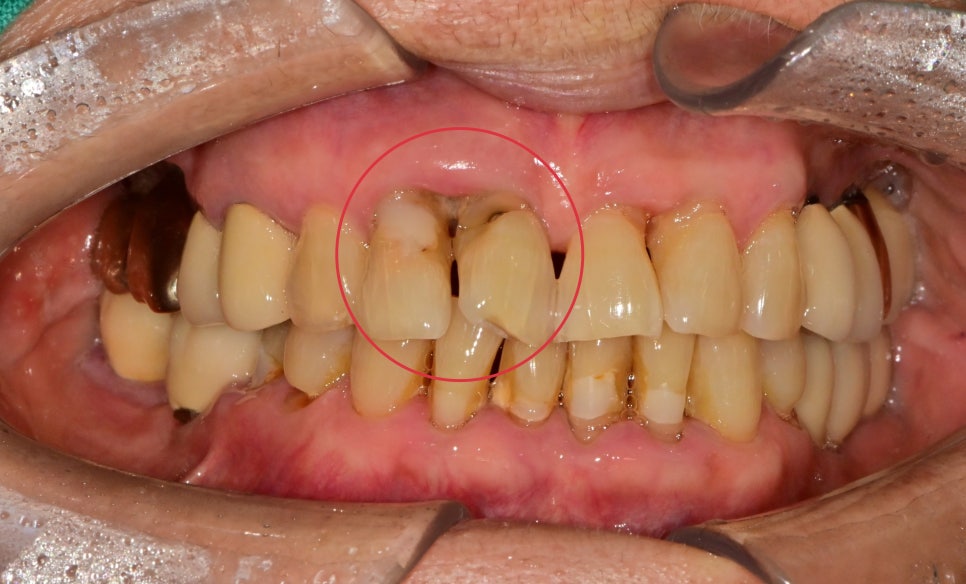

자고 일어나면 잇몸에서 피가 나요

앞니 2개 부분에서 잇몸도 붓고 피가 자주 난다고 내원해 주셨습니다

치열이 틀어져 있고, 치아가 너무 붙어있어 그로 인한 치주의 구조 자체가

치주 질환이 생길 수밖에 없는 구조였습니다